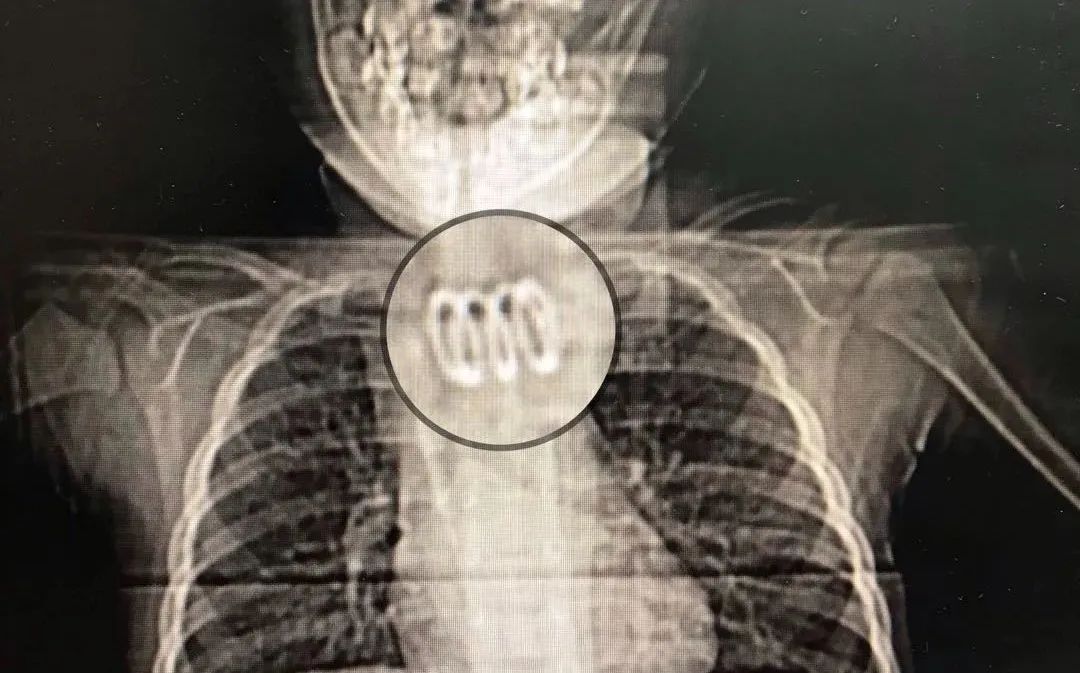

4月6日,阳阳因受凉后出现发热,最高体温39.5℃,又出现了明显喉鸣,而且只要吃颗粒状食物就引起吞咽困难,于是父母带他到湖北省妇幼保健院就诊。胸部CT检查中,影像科医生发现孩子颈部食管起始处有明显金属影,随即将他收治入院进行治疗。

当日,儿童消化科的医生通过胃镜探查发现有异物卡在了颈部食管,且疑似为弹簧。“我们想通过胃镜把这枚弹簧取出来,但弹簧的铁丝已经穿入食管,周围长了肉芽组织,尝试几次都无法用异物钳将它取出。”小儿胃镜室的朱珍妮医生介绍道。